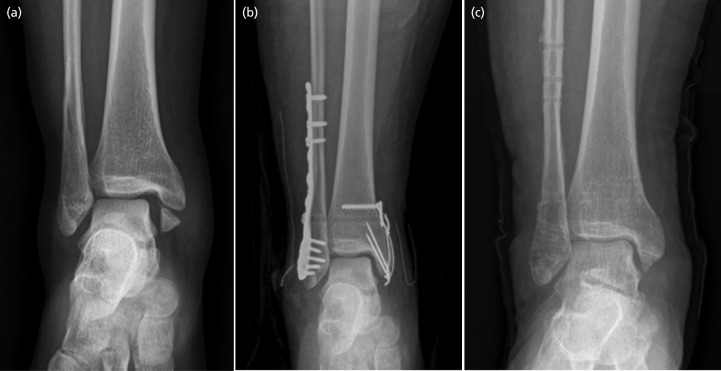

Materials and methods: Thirty patients were treated with dynamic fixation (DF group) and 28 patients with static screw fixation (SF group). The primary outcome was Olerud-Molander Ankle Outcome Score. The secondary outcome were Visual Analogue Scale score and American Orthopedic Foot and Ankle Society score, radiographic outcomes, complications and cost effectiveness. To evaluate the radiographic outcome, the tibiofibular clear space, tibiofibular overlap, and medial clear space were compared using the pre-operative and last follow-up plain radiographs. To evaluate the cost effectiveness, the total hospital cost was compared between the two groups.

Results: There was no significant difference in primary outcome. Moreover, there were no significant difference in secondary outcome including Visual Analogue Scale score and American Orthopedic Foot and Ankle Society score and radiographic outcome. Two cases of reduction loss and four cases of screw breakage were observed in the SF group. No complication in the DF group was observed. Dynamic fixation was more cost effective than static screw fixation with respect to the total hospital cost.